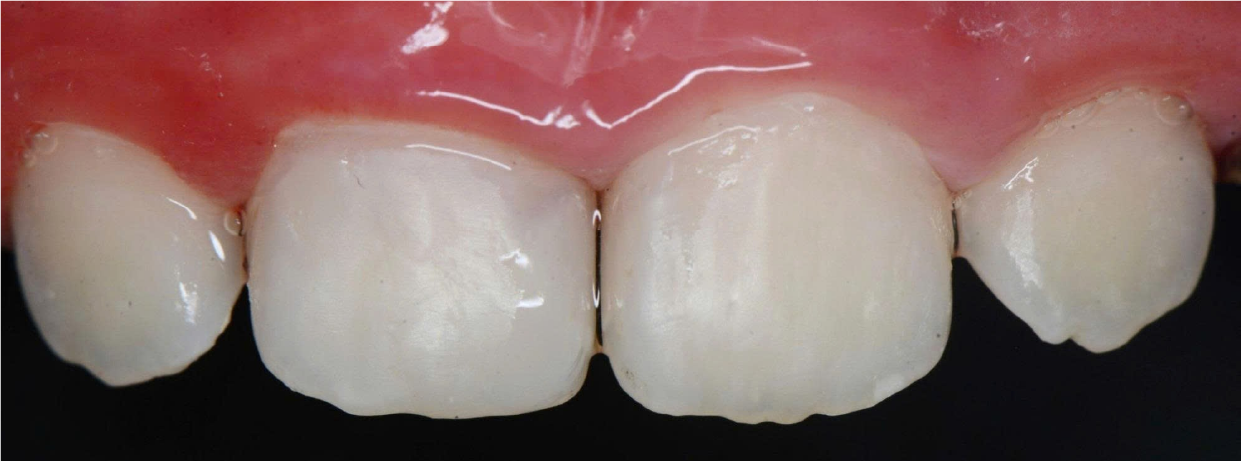

Hình Ảnh Trước & Sau Điều Trị

Minh chứng rõ ràng cho chất lượng và hiệu quả tại Nha khoa Như Ngọc – nơi mỗi khách hàng đều tìm lại được nụ cười tự tin sau quá trình điều trị và thẩm mỹ răng